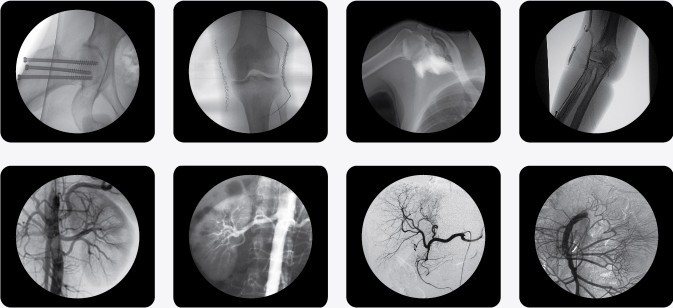

(普朗品牌產品-C型臂X光機PLX7000B)

南京普愛PLX7000系列高頻移動式C 形臂X射線機不但適用于以上介入手術的要求,同時還廣泛應用于骨科、外科、矯形外科、泌尿外科、脊柱外科、腹部外科、疼痛科、心臟科、消化科、婦科及手術室等。

其顯著優勢為:國內領先的全脈沖透視,智能曝光控制,實現超低輻射劑量;多葉與垂直光影控制,有效減少軟X線,大幅降低皮膚劑量;進口品牌影像增強器,全數字化CCD攝像機,提供高分辨的優質圖像;高分辨率雙液晶監視器,保證圖像效果;強大數字化圖文工作站標配DICOM3.0接口與網絡完美對接,支持Worklist登記和手動登記雙登記模式;工作站具有大容量數字化存儲功能,透視和數字點片均以數字化格式無損存儲,邊緣增強 多重鏡像 gamma校正、電影回放、窗寬窗位、專家模板、刻錄等強大處理功能;四維電動運動控制,定位精確,靈活自如;超大機架設計,提供了超大的診視空間,更加舒適的手術環境;全新設計,全新理念、帶來超凡體驗;雙面板人體圖形化液晶觸摸屏,操作智能快捷;雙運動控制系統、雙曝光腳閘設計,極大滿足臨床操作。